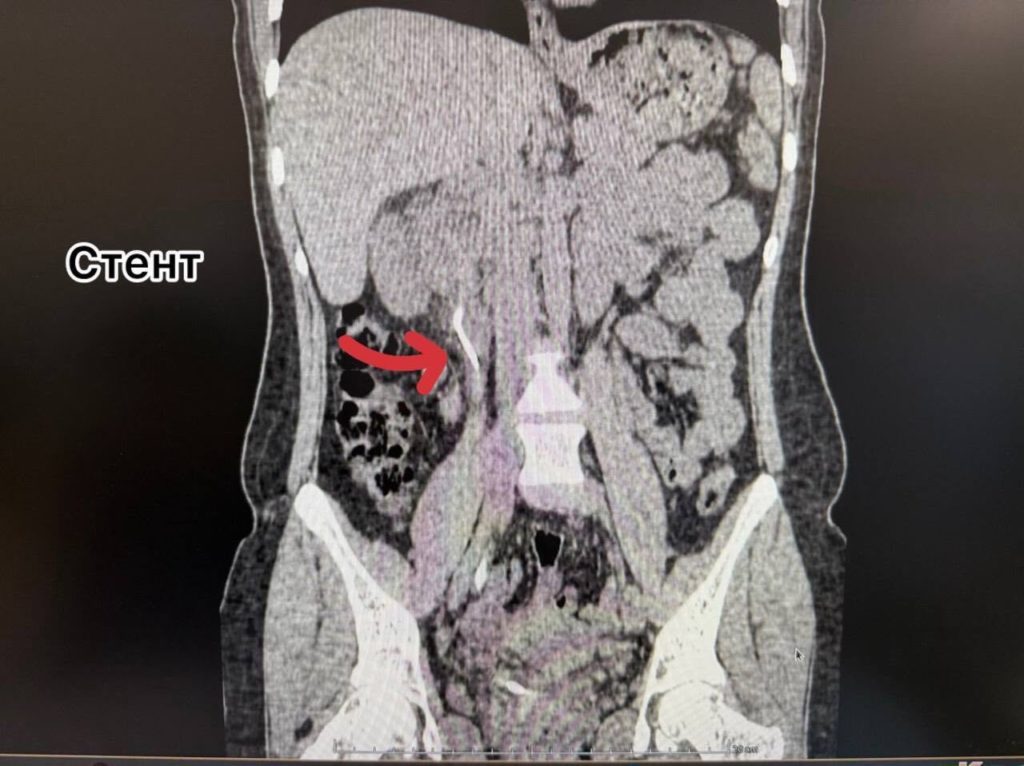

За это время на трубке образовались солевые отложения, сформировавшие крупные камни как в почке, так и в мочевом пузыре.

Помощь была оказана в приоритетном порядке по системе «зелёного коридора», так как пациентка является супругой участника СВО. Перед врачами стояла сложная трёхэтапная задача: удалить камень из почки, раздробить и извлечь камень из мочевого пузыря и убрать сам инкрустированный стент.

Урологи Александр Певчев и Мадина Абдуллаева провели уникальное сочетанное вмешательство за одну операцию. Через минимальный прокол в пояснице ультразвуком был разрушен почечный камень, а через естественные пути лазером раздроблены и удалены камень из мочевого пузыря и стент. Вся процедура выполнялась с эндоскопическим и рентгенологическим контролем.